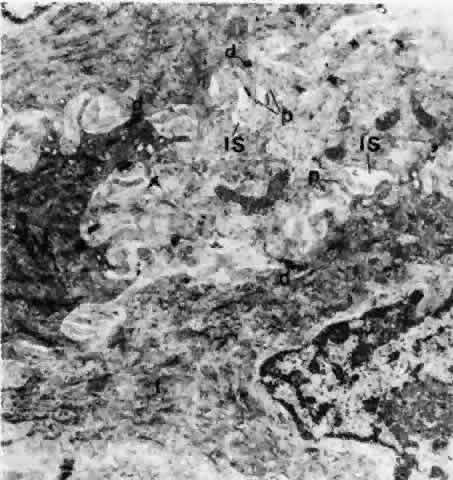

The structure of the conjunctival epithelium can be related to its functions. Smaller interepithelial openings measure 1 to 3 μm, which can be appreciated with a scanning electron microscope (Fig. 10), and these are openings of interepithelial goblet cells. Larger openings (10 to 60 μm) are the openings of the epithelial rugae, which are produced by numerous interepithelial glands. At the surface, the intercellular spaces are completely closed by tight junctions. Beneath the surface, extensions of the cytoplasm (microvilli) protrude into the intercellular spaces, which are occasionally connected by desmosomes.20 These microvilli can also be seen on the epithelial cell surface. The basal epithelial cells are attached to the quite thick basement membrane by hemidesmosomes.20

Fig. 10. Middle layer of bulbar conjunctival epithelium showing widened intercellular spaces, into which small cytoplasmic processes are protruding. Relatively few desmosomes are shown. Tonofilaments (t) tend to form bundles. IS, intercellular space; d, desmosomes; p, cytoplasmic processes. (× 20,800)